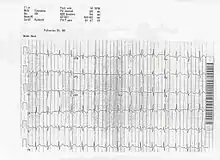

On ECG a left axis deviation is generally found in ostium primum ASD, but an RSR pattern (M pattern) in V1 is characteristic. Fixed splitting of the second heart sound (S2) occurs because of equal filling of the left and right atria during all phases of the respiratory cycle.

Patients with atrial Septal Defects may have atrial fibrillation, atrial tachycardia, or atrial flutter, but these abnormal heart rhythms are not usually seen until the affected individual grows older. Features also seen on the ECG include right atrial enlargement and varying degrees of atrioventricular block. When a person is suspected of having an ASD based on the findings of an incomplete right bundle branch block with a rSr' or rSR', the frontal plane QRS should be examined. The frontal plane QRS is the most helpful clue to distinguish between an ostium secundum ASD and an ostium primum ASD. In primum defects left axis deviation is seen in most patients with an axis of > -30 degrees and very few patients have right axis deviation. In contrast ostium secundum defects have an axis between 0 degrees and 180 degrees with most cases to the right of 100 degrees.

In the ECG above, you can see an example of the rSR' pattern in V1 with a R' greater than S with T wave inversion which is commonly seen in volume overload right ventricular hypertrophy.